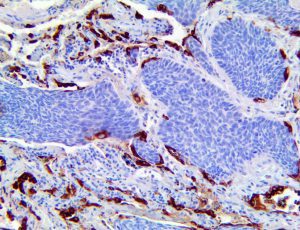

The first cytokines released are interleukin 1β (IL-1β) and tumor necrosis factor-α (TNF-α), which attract a variety of circulating white blood cells (WBCs) to the infection site, including neutrophils, monocytes, macrophages, and natural killer (NK) cells. This response, along with the antipathogenic chemicals released by these cells (i.e., complement), comprise the innate immune response. These cells directly attack the invading pathogen and also release additional cytokines, chief among them interleukin-1 and 6 (IL-6). IL-6 is essential for invoking the adaptive immune response, which calls T-cells, B-cells, and T helper (Th) cells to the infection site. IL-6 also stimulates further recruitment, proliferation and activation of macrophages.

This activation induces inflammatory monocytes to highly express IL-6, starting a localized and then systemic cascade effect that results in hyperproduction of IL-6, which accelerates the inflammatory process. Because IL-6 also increases vascular permeability, excessive levels cause blood vessels to become very leaky. This, along with clotting factors released from vascular endothelial cells, stimulates the coagulation cascade, resulting in microthrombosis (tiny clots), which leads to ischemia and tissue death of the kidney, intestines, heart, liver, brain and extremities.